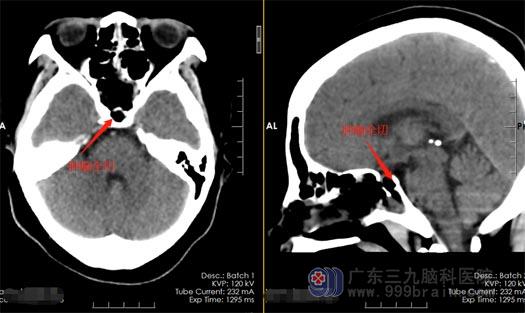

完善相关检查与术前准备以后,黄女士接受了神经外五科治疗团队施行的“内镜经鼻蝶鞍区占位病变切除术”,手术很顺利,肿瘤被完整的去除了。术后的黄女士视力得到明显的改善。

▲术后